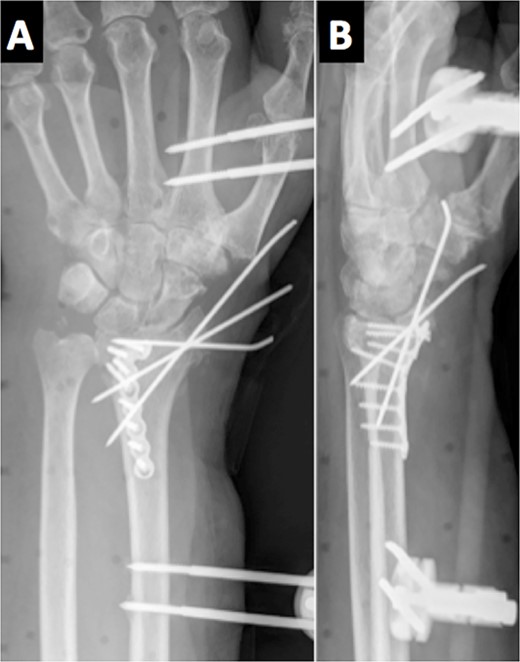

Due to the comminuted fracture and the bone osteoporosis, the final decision was closed reduction and fixation with K-wires. Due to the inadequate reduction, we decided to associate an external fixator. However, during surgery, an inadequate reduction of the ulnar column was observed, and thus, a mixed synthesis with an L-shaped plate was added (Fig. 2).